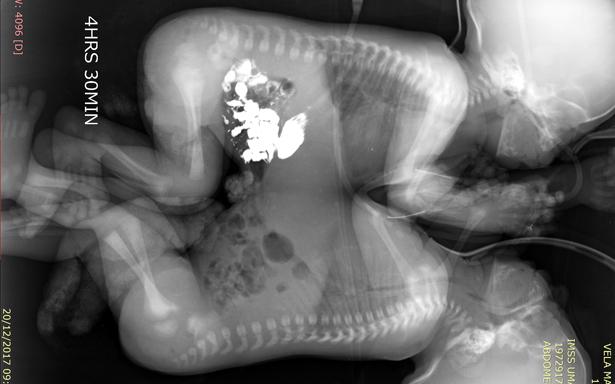

Tras diversos exámenes de tomografía, ecocardiograma y resonancia magnética, cuando los niños cumplieron 41 días de vida, fueron programados para la cirugía que los separaría.

El equipo multidisciplinario de cirujanos, anestesistas y enfermería, dio inicio a la operación a las 9:00 horas; de manera cuidadosa realizaron la incisión en la línea media que unía a los gemelos y mediante la técnica de electrocoagulación, lograron separarlos a las 12:43 horas, sin que se presentaran complicaciones.